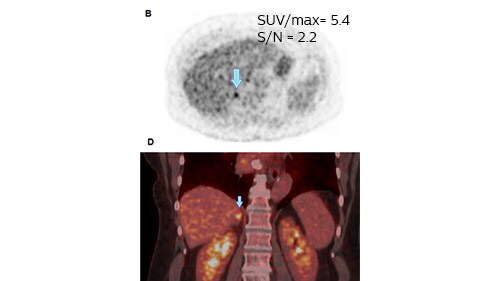

Case study of metastatic adrenal gland

Clinicians at Isala also recently published a case study² that reported results from a scan of a 68 year-old woman suspected of lung cancer, who underwent a whole body FDG-PET scan.

Figure 1: The 4 mm voxel reconstruction shows no enlargement of the gland in CT and a slightly increased FDG uptake. The gland was considered benign and combined chemotherapy was initiated.

Figure 1: The 2 mm voxel reconstruction showed a higher SUVmax and a higher contrast despite increased noise. The gland was considered suspicious and more likely to be metastatic.